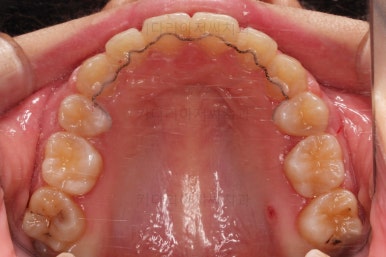

부산연산동교정치과 치료 종료 시의 모습이에요.

삐뚤한 치열도 가지런해졌고 2급 부정교합도 정상교합으로 맞춰졌어요.

튀어나와있던 앞니도 좋아졌고, 과개교합도 개선이 되었어요.

옆라인도 좋아졌고 입술을 다무는 느낌이 굉장히 편안해져서 입이 많이 들어간 건 아닌듯하지만 얼굴모습은 매우 좋아졌어요.

전후 사진을 비교해 보겠습니다.

전후 사진을 나란히 놓고 비교해 보면 굉장히 많이 좋아진 것을 볼 수 있으실거에요.

웃을 때의 치아의 위치를 보면 뒤로 들어간 것을 볼 수 있고, 이 영향으로 입매도 매우 예뻐졌고 편안해졌어요.

교합이나 치아배열의 모습도 좋아졌고요.

특히 관리가 힘들어 썩었던 치아도 충치치료 없이 발치교정할 수 있었고요.

남아있는 충치는 치료해야 되지만 교정치료는 잘 마무리 되었어요.